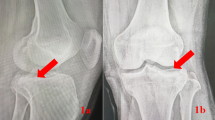

Traditional concepts and the literature worldwide support the consensus that surgery should only be performed after the swelling subsides to prevent serious consequences such as soft tissue necrosis, wound dehiscence, and exposed plates (Fig. 1A)13,14. The waiting period for swelling reduction and staged surgery significantly prolongs the treatment duration and is associated with various complications, as well as increasing the financial burden on patients and society. However, no technology or concept is currently available to circumvent this issue. Negative pressure wound therapy (NPWT) has become an important treatment modality for various types of wounds and is suitable for the treatment of surgical wound dehiscence, deep pressure injury, diabetic foot ulcer, infection, limb soft tissue injury, open fracture, and skin grafting15,16. NPWT provides a closed, sterile, and relatively moist environment for wound tissue and is conducive to granulation tissue proliferation. Simultaneously, it accelerates local blood microcirculation, promotes drainage, prevents infection, and creates favourable conditions for wound healing17.

In this study, we applied a novel wound management strategy for the treatment of tibial plateau fractures with soft tissue swelling, aiming to investigate the feasibility and clinical efficacy of this approach. Our objective was to provide orthopedic surgeons with new perspectives and evidence to support clinical decision-making. For TPFs without congestive blisters, we hypothesized that the use of open reduction and internal fixation in the early stage of swelling, followed by wide-spacing interrupted sutures and NPWT to close the wound, would accelerate swelling reduction, promote wound healing, and avoid adverse outcomes (Fig. 1B). We describe our novel early surgical wound management techniques and concepts in this setting, which expand the surgical indications for TPFs with soft tissue swelling compared to conventional wisdom. We compared the new wound management model with traditional surgery regarding perioperative indices, joint function and imaging efficacy, preoperative and postoperative complications, and quality of life, providing new ideas and a basis for clinical surgical decision-making.